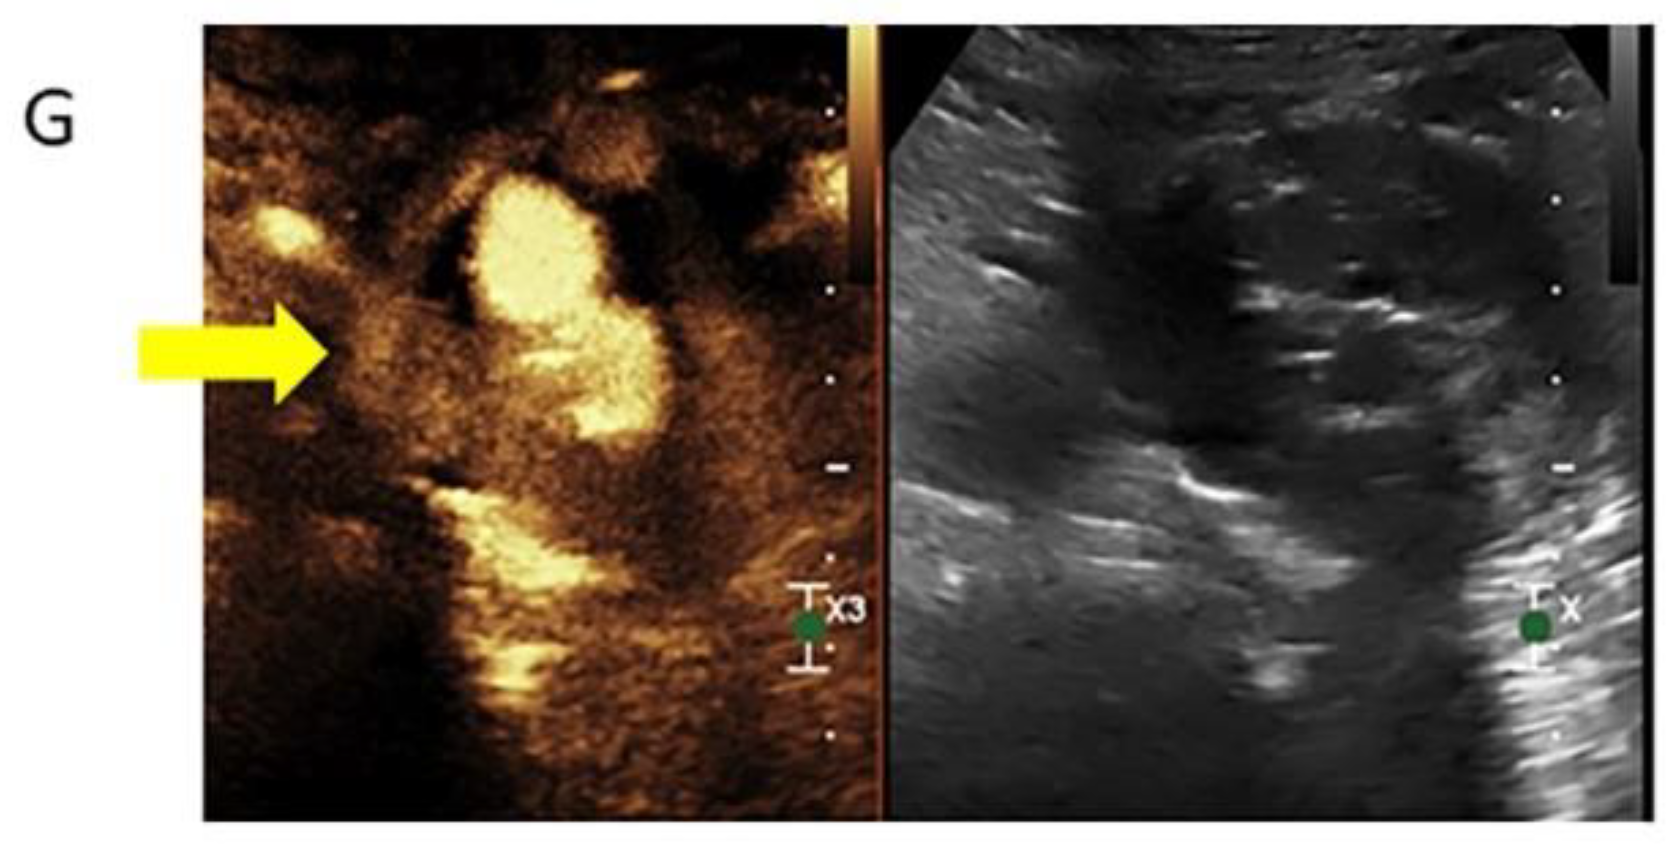

3.2.3. Contrast-Enhanced Ultrasound

- Bredahl, K.; Mestre, X.M.; Coll, R.V.; Ghulam, Q.M.; Sillesen, H.; Eiberg, J. Contrast-Enhanced Ultrasound in Vascular Surgery: Review and Update. Ann. Vasc. Surg. 2017, 45, 287–293. [Google Scholar] [CrossRef] [PubMed]

- Huang, D.Y.; Yusuf, G.T.; Daneshi, M.; Ramnarine, R.; Deganello, A.; Sellars, M.E.; Sidhu, P.S. Contrast-enhanced ultrasound (CEUS) in abdominal intervention. Abdom. Radiol. 2018, 43, 960–976. [Google Scholar] [CrossRef] [PubMed]

- Marschner, C.A.; Rübenthaler, J.; Froelich, M.F.; Schwarze, V.; Clevert, D.-A. Benefits of contrast-enhanced ultrasonography for interventional procedures. Ultrasonography 2021, 40, 207–216. [Google Scholar] [CrossRef] [PubMed]